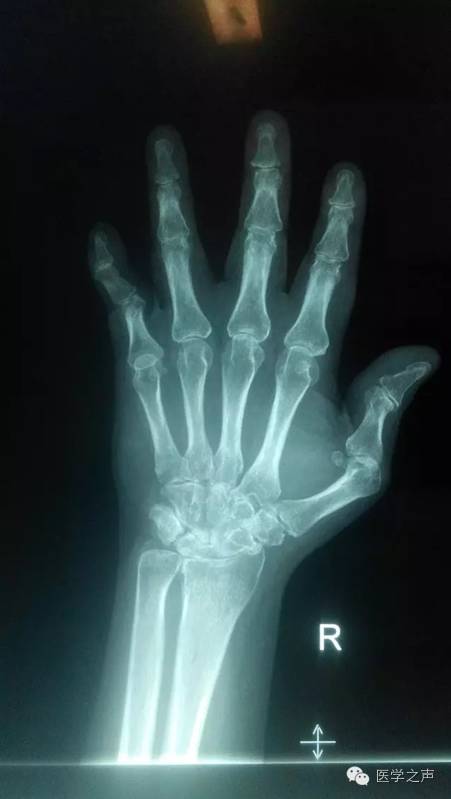

【病例】双手类风湿性关节炎1例X线影像表现

影像表现:

双手指间关节周围软组织稍肿胀,关节面模糊,关节间隙变窄,关节邻近骨质疏松,其间可见斑点状及小囊状骨质密度减低区,左手第1掌指关节及右手第5指关节呈半脱位,各腕骨骨质疏松,边缘不清,见斑点状及小囊状骨质密度减低区。

诊断意见:

1.双手类风湿性关节炎。

2.左手第1掌指关节及右手第5指关节呈半脱位。